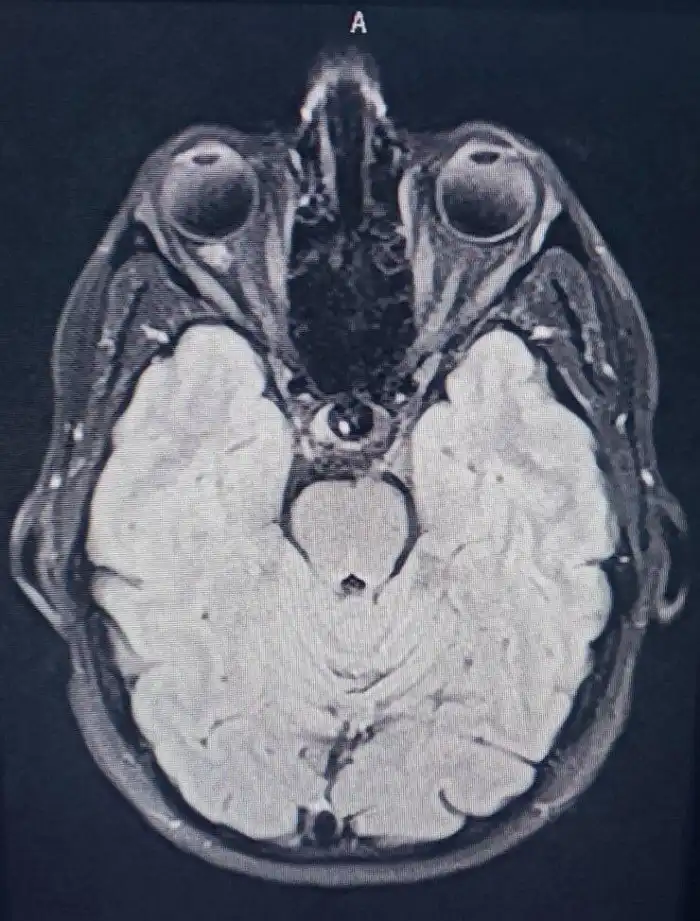

Скан головного мозга яеловека. Место схождения нервных пучков, идущих от глаз к мозгу, напоминает третий глаз